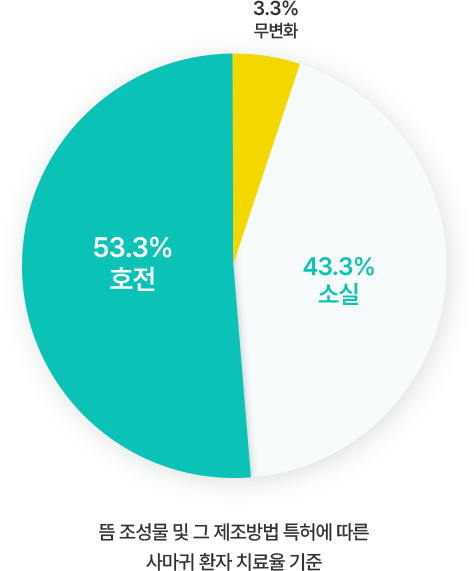

의료 정보 자문 및 도움말